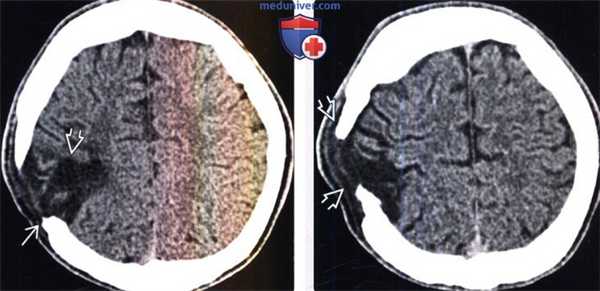

(Слева) Бесконтрастная КТ, проводимая в рамках рутинного наблюдения за пациентом в динамике, аксиальный срез: у юноши 14 лет через два месяца после эвакуации субдуральной гематомы, образовавшейся вследствие футбольной травмы, определяется дефект черепа и посттравматическая энцефаломаляци.

(Справа) Два года спустя тот же пациент стал наблюдать постепенное увеличение «шишки» на голове. При повторной бесконтрастной КТ определяется, что края дефекта черепа выступает наружу, а через сам дефект выпячивается объемное образование с плотностью, подобной ликвору, которое располагается под сухожильным шлемом.